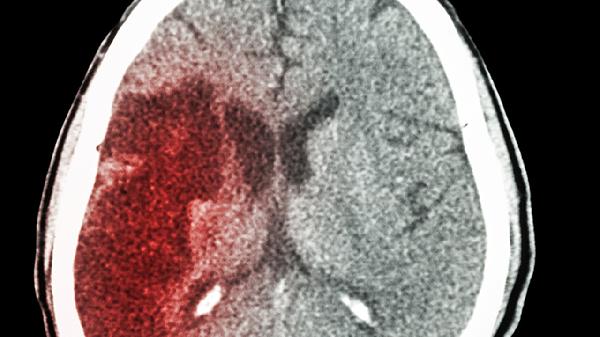

脑梗患者出现呕吐时需立即就医,通过头颅CT或MRI明确梗死部位和范围。对于颅内压增高者,医生可能使用甘露醇注射液或呋塞米注射液降低颅压,同时需监测电解质平衡。伴有前庭症状者可遵医嘱使用甲磺酸倍他司汀片改善微循环。日常护理应保持侧卧位防止误吸,记录呕吐频率和性状,避免擅自使用止吐药物掩盖病情变化。